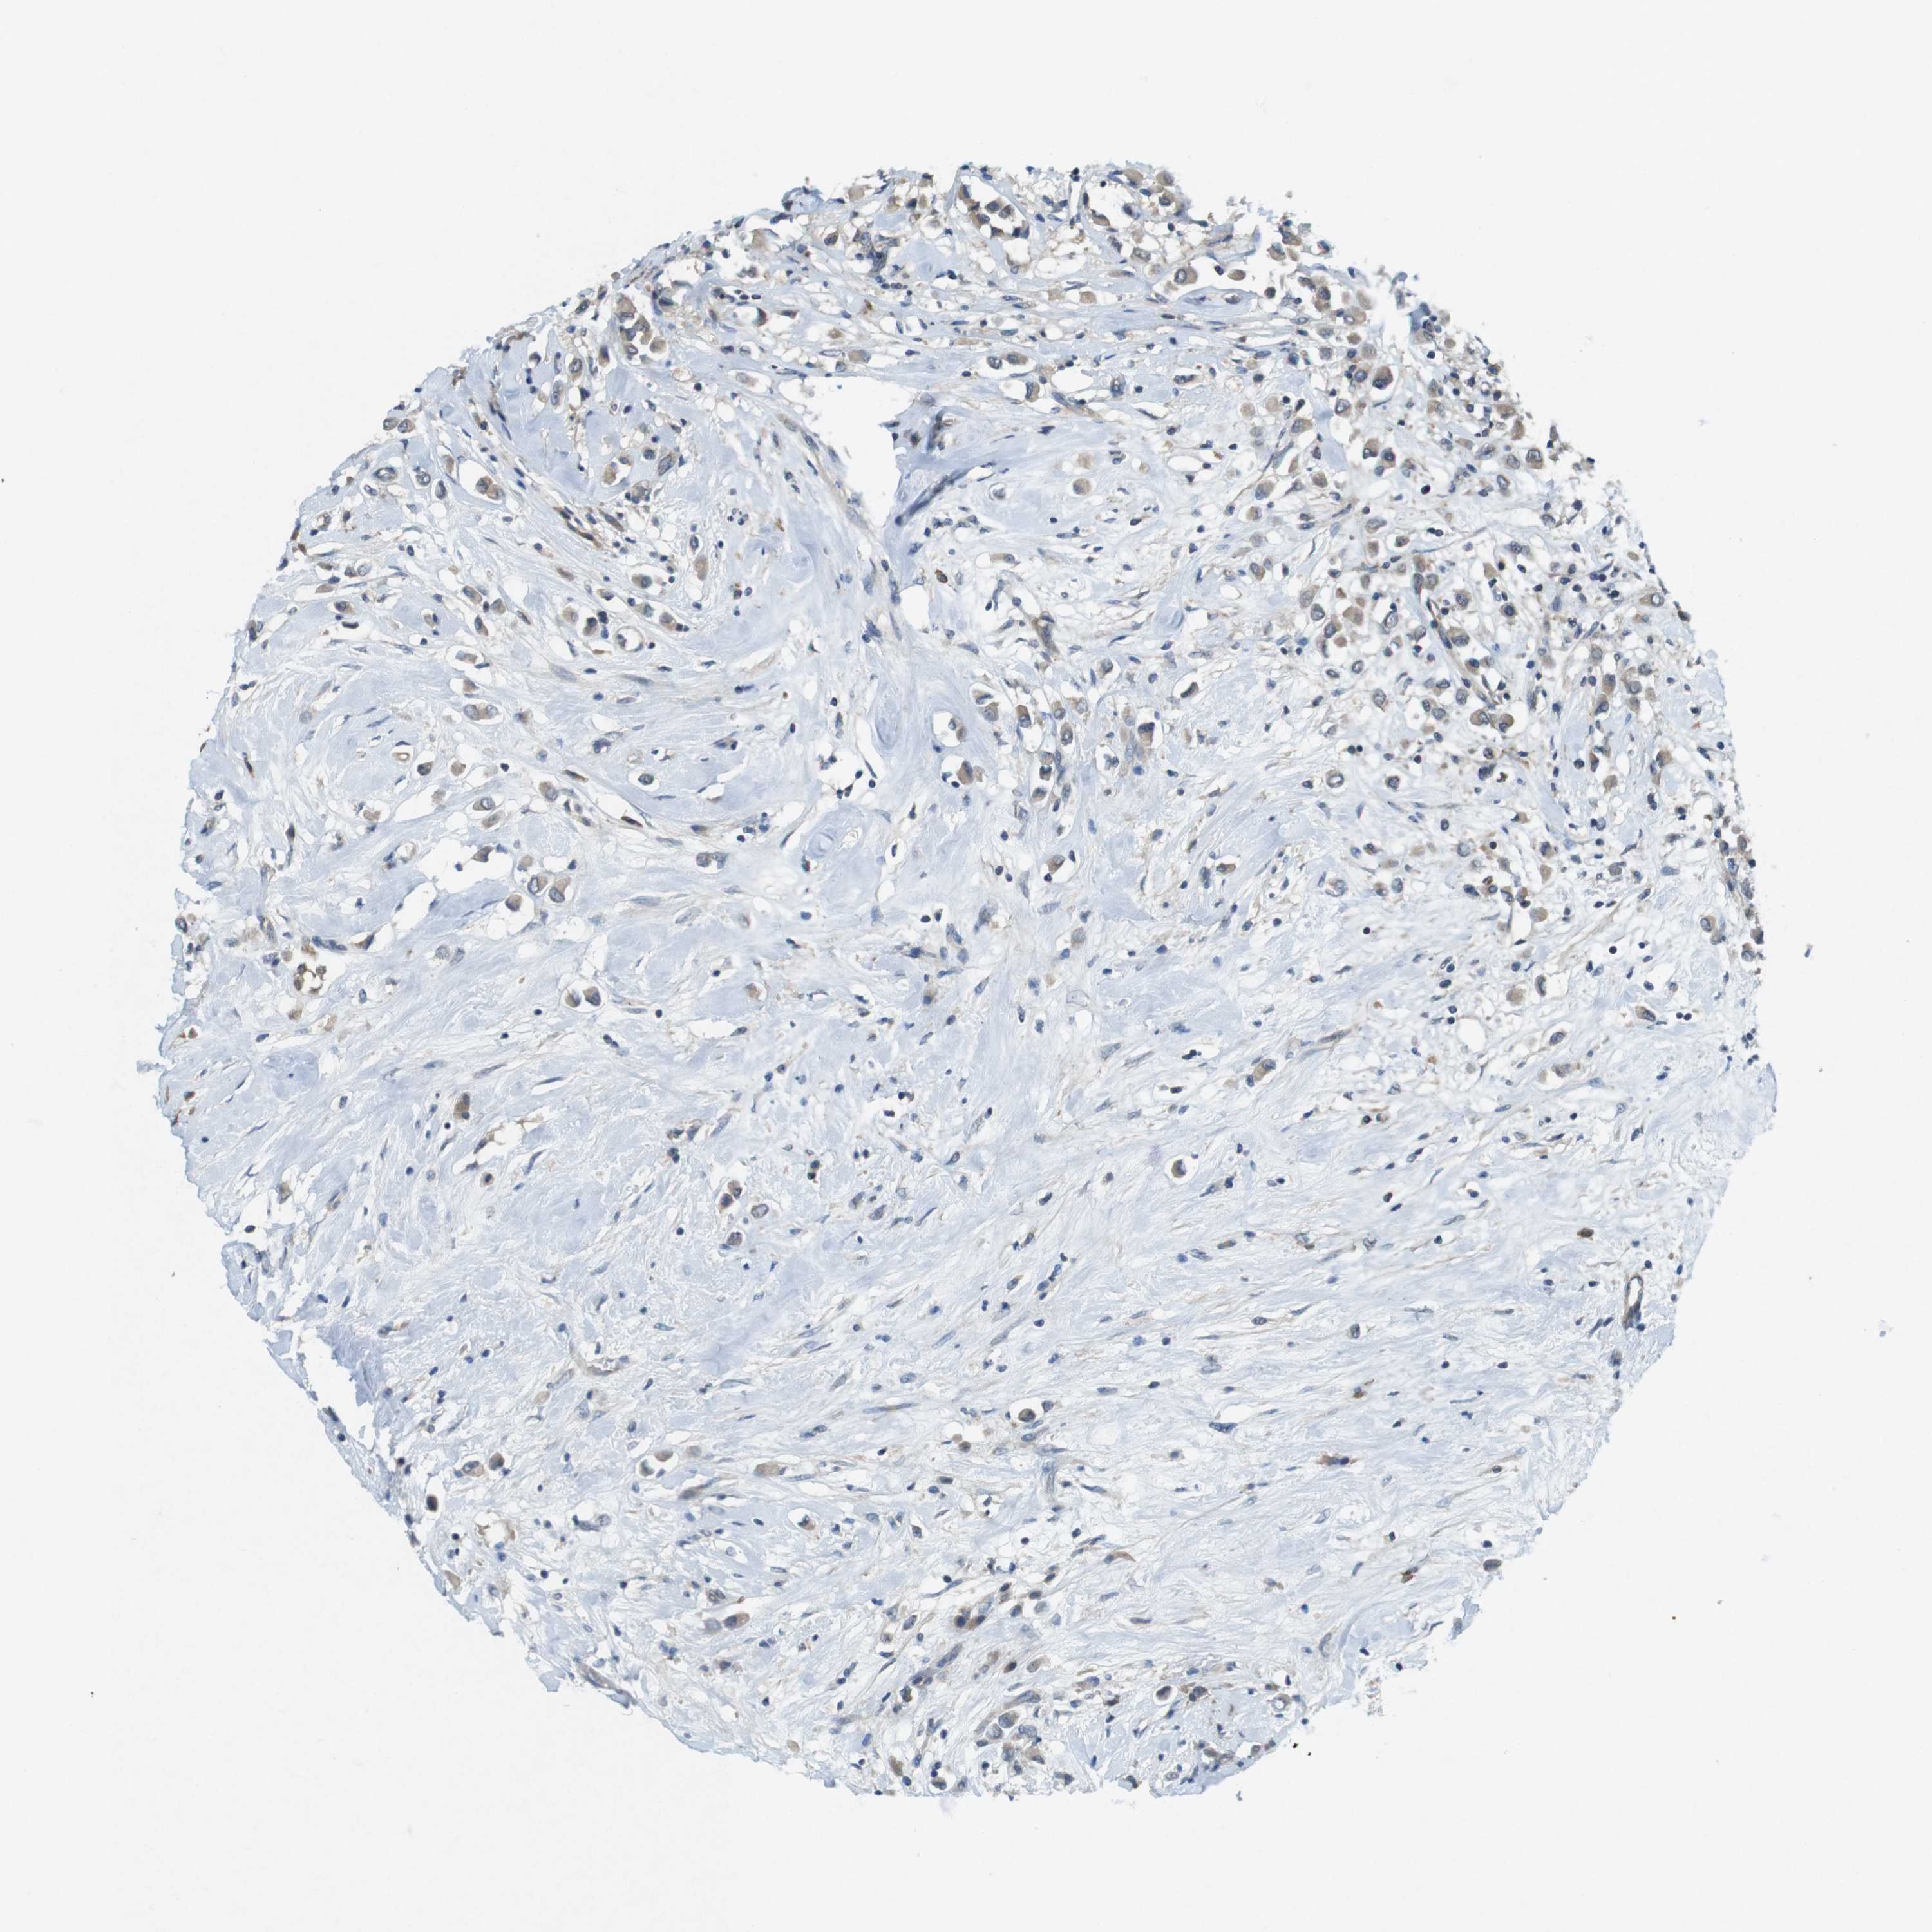

CANCER BREAST CANCER Show tissue menu

BRCA TCGA BRCA VALIDATION PROTEIN EXPRESSION

SUGT1 is not prognostic in Breast Invasive Carcinoma (TCGA)

Average pTPM 41.4

Number of samples 1022